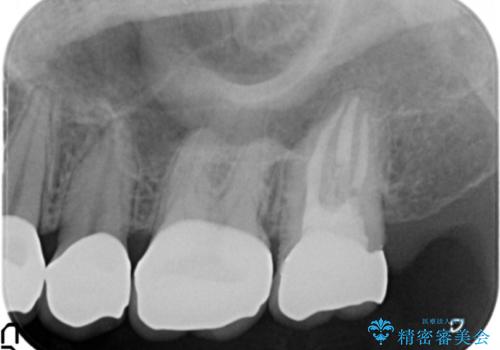

精査したところ、ほとんどの歯が保険内のレジンで充填されており、咬み合わせも悪く咬合していない歯もありました。

虫歯をしっかりと治療したのち、オールセラミッククラウンによる補綴治療を行いました。

下顎の埋伏していた親知らずも抜去しました。